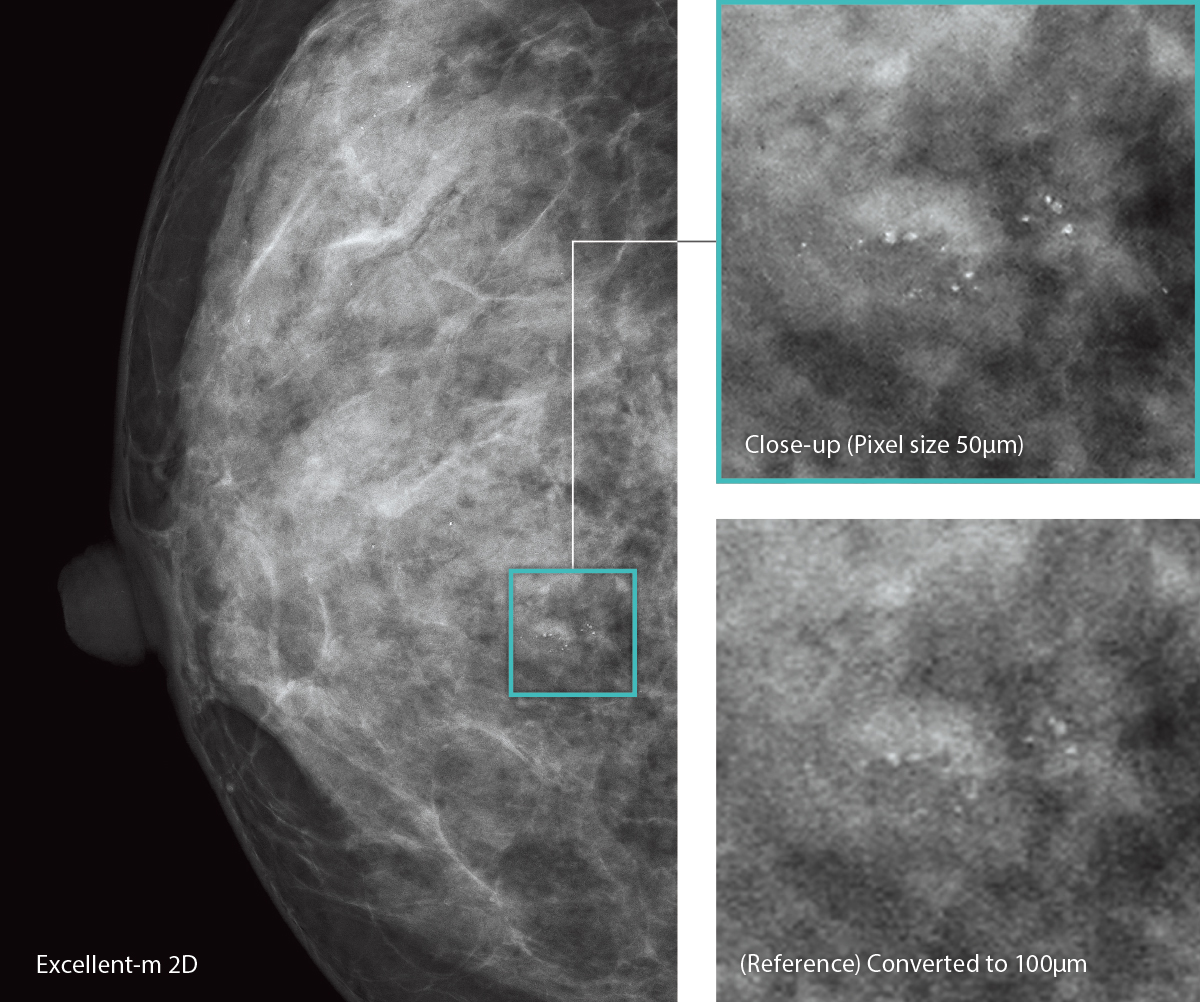

AMULET Innovality employs a direct-conversion flat panel detector made of Amorphous Selenium (a-Se) which exhibits excellent conversion efficiency in the mammographic X-ray spectrum. The HCP (Hexagonal Close Pattern) detector efficiently collects electrical signals converted from X-rays to realize both high resolution and low noise. This unique design makes it possible to realize a higher DQE (Detective Quantum Efficiency) than with the square pixel array of conventional TFT panels. With the information collected by the HCP detector, AMULET Innovality creates high definition images with a pixel size of 50 μm; the finest available with a direct-conversion detector.